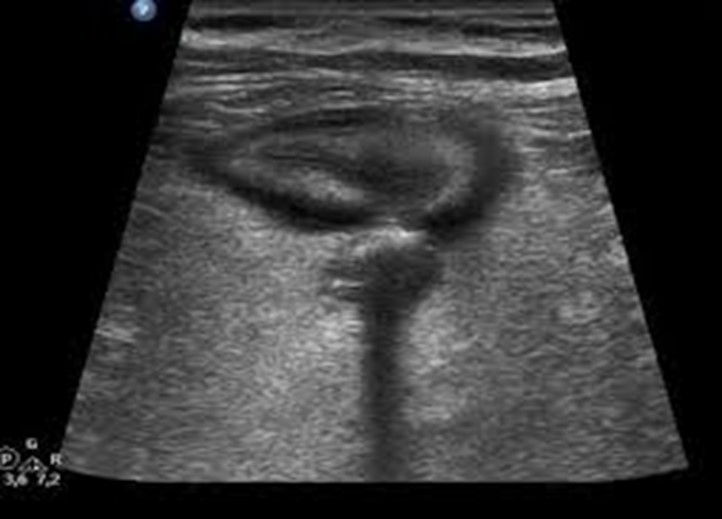

Ghi nhận hình ảnh trên siêu âm:

Cấu trúc hình ống đầu tận d= 8mm  nằm ở vùng bụng dưới bên phải ấn không xẹp ,thành ruột thừa  dày và phù nề hình bia bắn mô mỡ xung quanh ruột thừa tăng âm (tăng sáng) do phản ứng viêm.

Hình ảnh viêm túi thừa manh tràng : hình ảnh rải rác vài túi thừa tại manh tràng cấu trúc hình túi,mô mỡ thâm nhiễm dày, phản ứng viêm xung quanh;